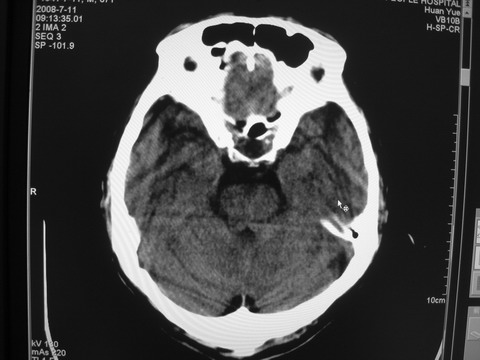

患者 男 69岁 头晕头痛不适

多发病灶,指状水肿,首先诊断转移瘤。

多个结节并周围大面积水肿区,多考虑多发性脑转移瘤

小病灶、大水肿,病灶多发,首先考虑多发转移瘤;建议查原发灶。

额顶叶多发小病灶、大水肿,首先考虑多发转移瘤;建议查原发灶

脑内多发病灶,小病灶,大水肿。

典型转移性肿瘤。

应进一步检查,查找原发病灶。

结果 : 该患者结肠癌病史5年 考虑脑转移